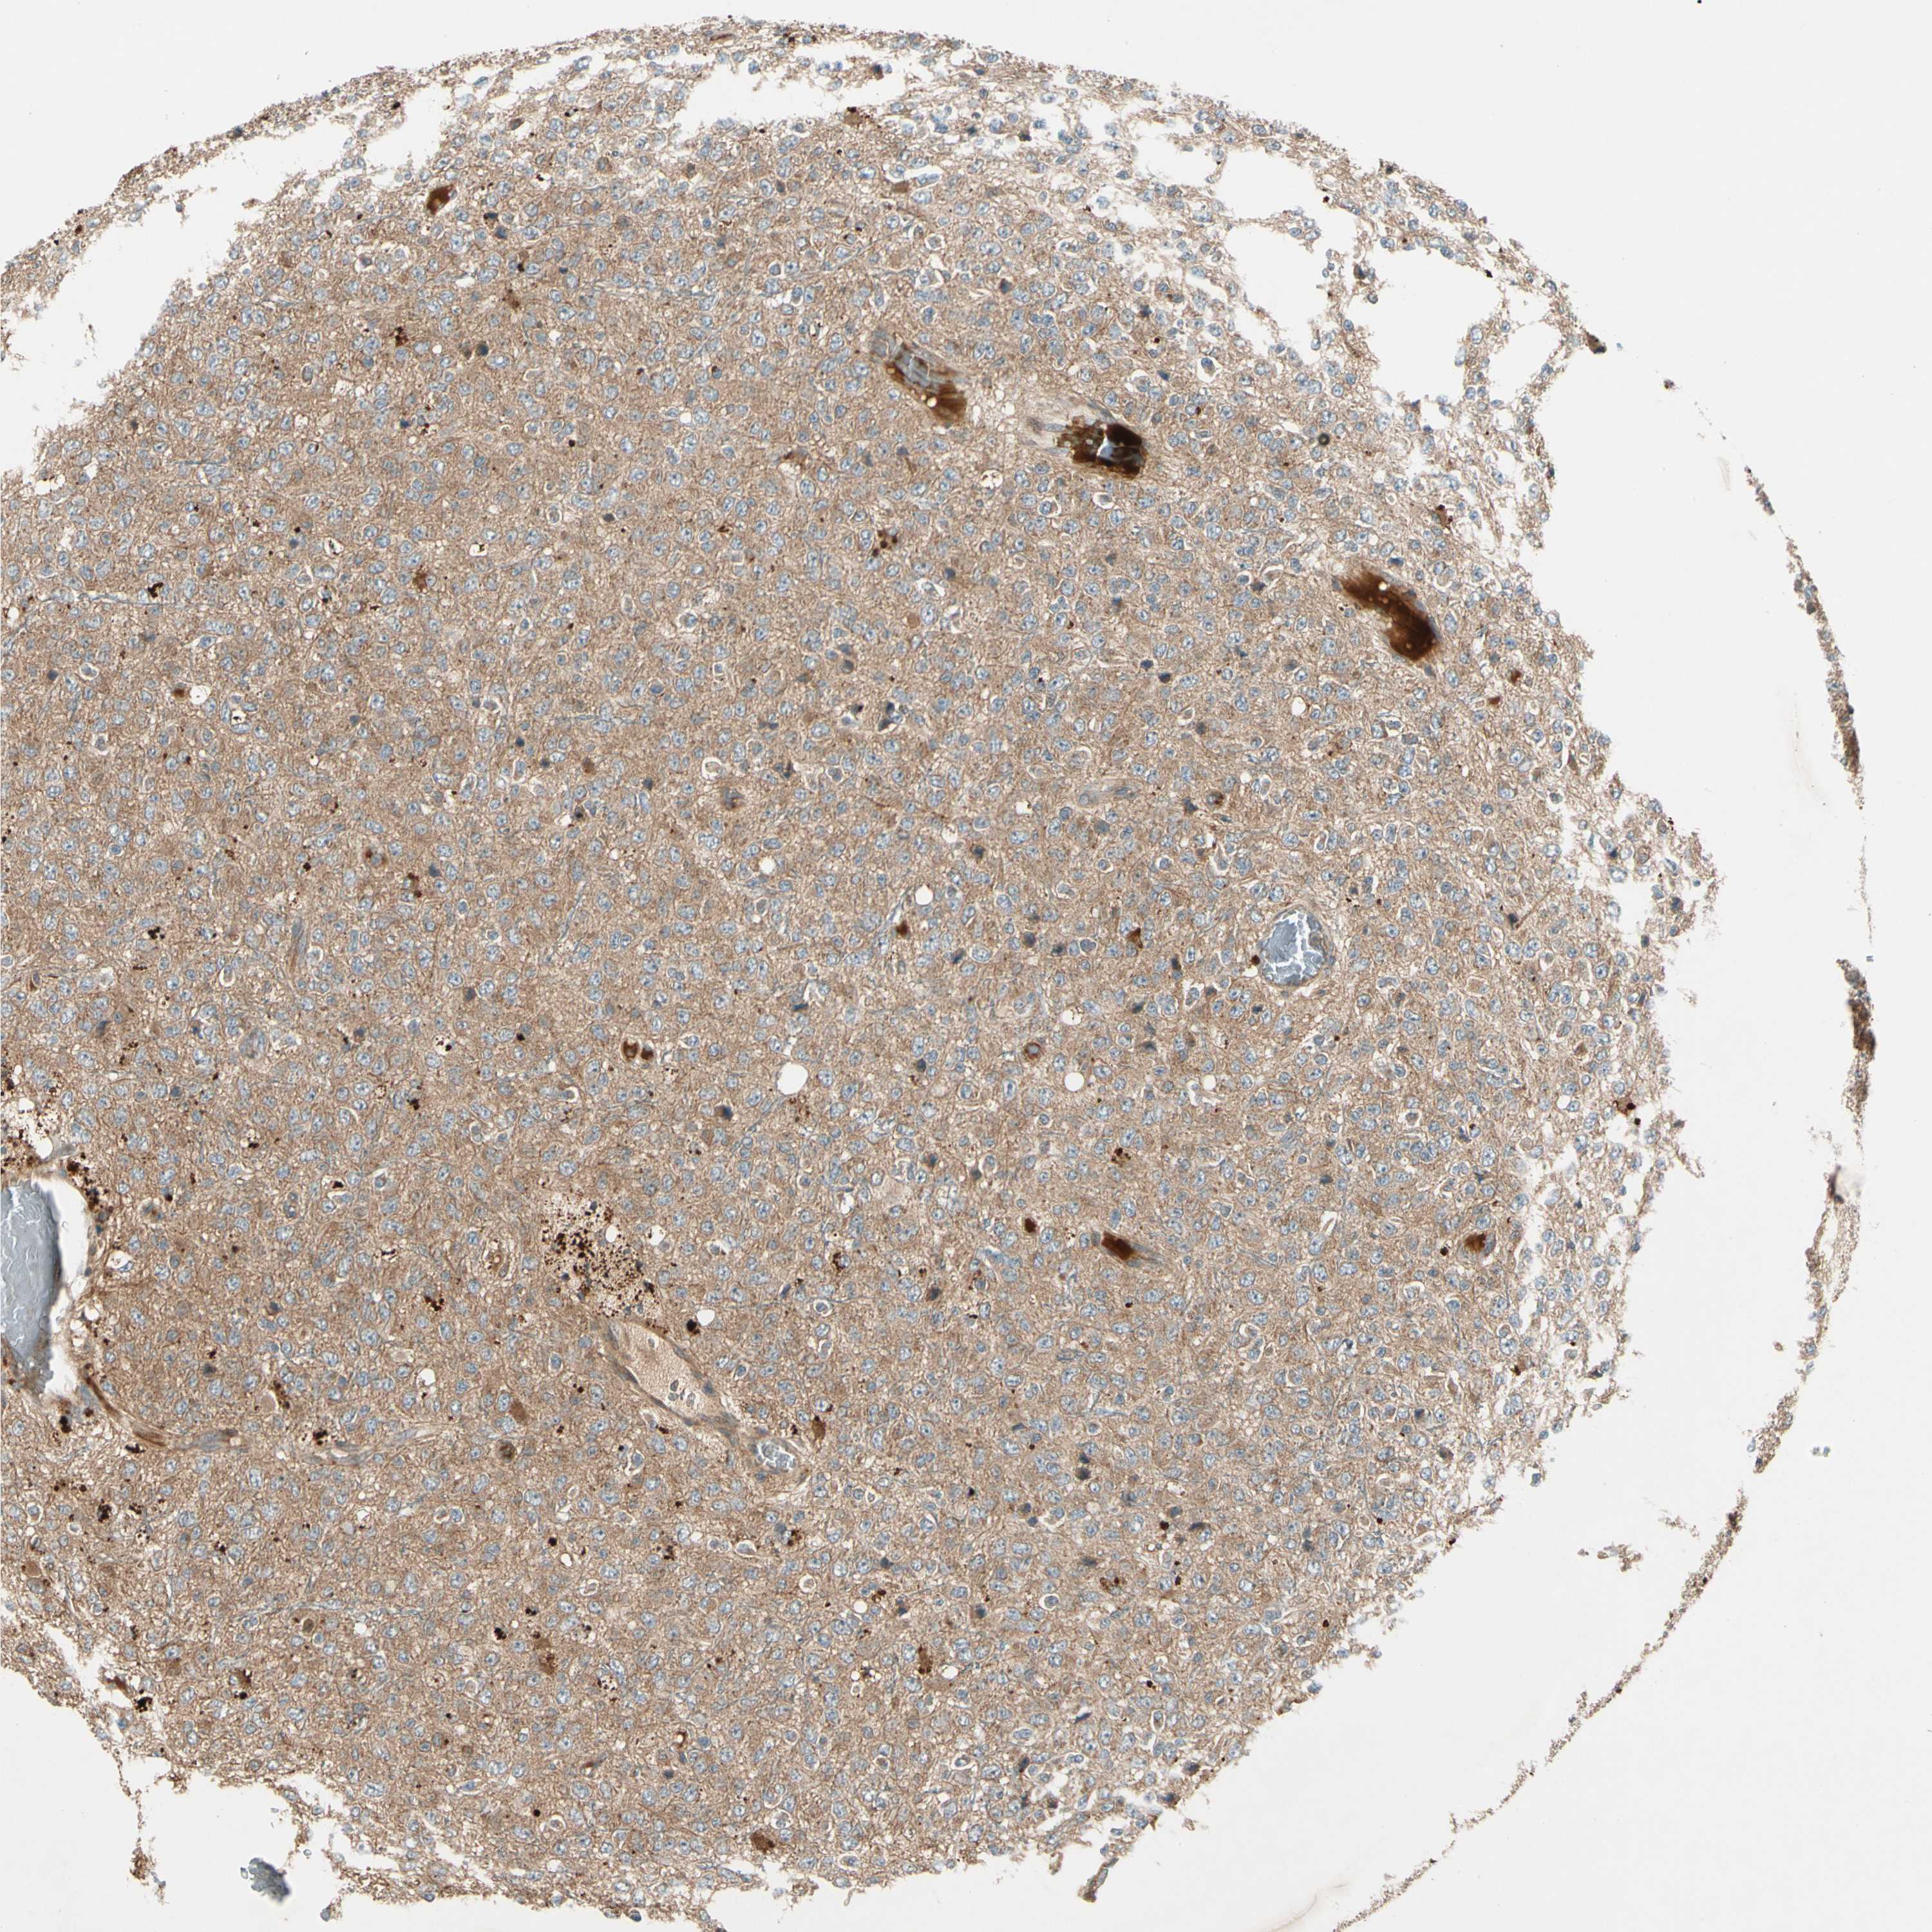

GLIOMA - Protein expressioni

A mouse-over function shows sample information and annotation data. Click on an image to view it in a full screen mode. Samples can be filtered based on level of antibody staining by selecting one or several of the following categories: high, medium, low and not detected. The assay and annotation is described here.

Note that samples used for immunohistochemistry by the Human Protein Atlas do not correspond to samples in the TCGA dataset.

Antibody stainingi

Antibody staining in the annotated cell types in the current human tissue is reported as not detected, low, medium, or high, based on conventional immunohistochemistry profiling in selected tissues. This score is based on the combination of the staining intensity and fraction of stained cells.

Each image is clickable and will lead to virtual microscopy that enables deeper exploration of all samples and also displays staining intensity scores, fraction scores and subcellular localization as well as patient and tissue information for each sample.

Antibody HPA007982

Antibody HPA011933

Staining

High

Medium

Low

Not detected

Intensity

Strong

Moderate

Weak

Negative

Quantity

>75%

75%-25%

<25%

None

Location

Nuclear

Cytoplasmic/membranous

Cytoplasmic/membranous,nuclear

Glioma, malignant, High grade

Glioma, malignant, Low grade